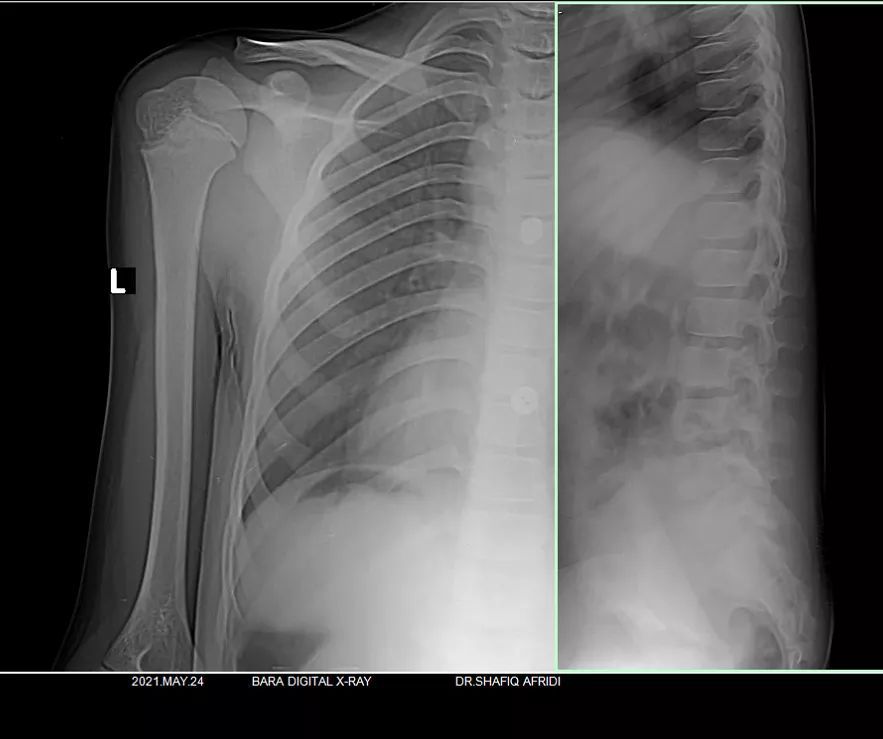

Fructure

Treatment

Spotdignosis